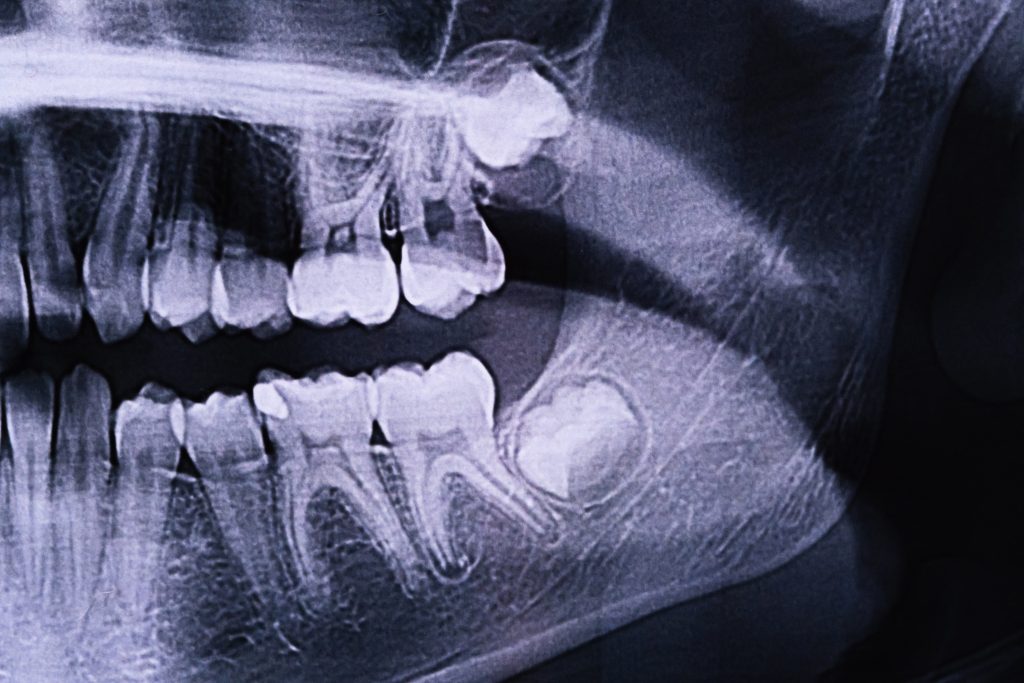

Panoramic X-ray

Identifying impacted teeth early greatly increases the chances of successful treatment. A panoramic x-ray and clinical exam can confirm whether all adult teeth are present or if some are missing. For younger patients, early detection allows for intervention before the impacted tooth becomes fused in place.